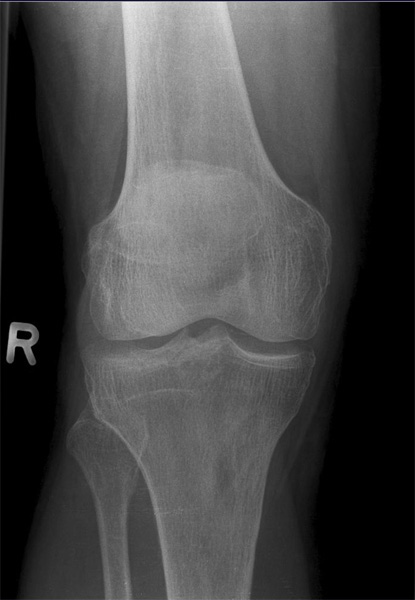

Knie seitlich

126_5.jpg

Fehler

Die filmferne Femurrolle "rutscht" mit ihrer Konturlinie nach unten und überdeckt die ganze Eminetia intercondylaris. Das Knie ist seitlich getroffen, jedoch war der Unterschenkel nicht auf einer Höhe mit dem Oberschenkel.

Abhilfe

Richtige Zentrierung, streng seitlich, aber auch präzise Lagerung des Knies und des ganzen Beines, wobei die Ferse mit einem Keilkissen angehoben wird (nicht zu viel und nicht zu wenig).